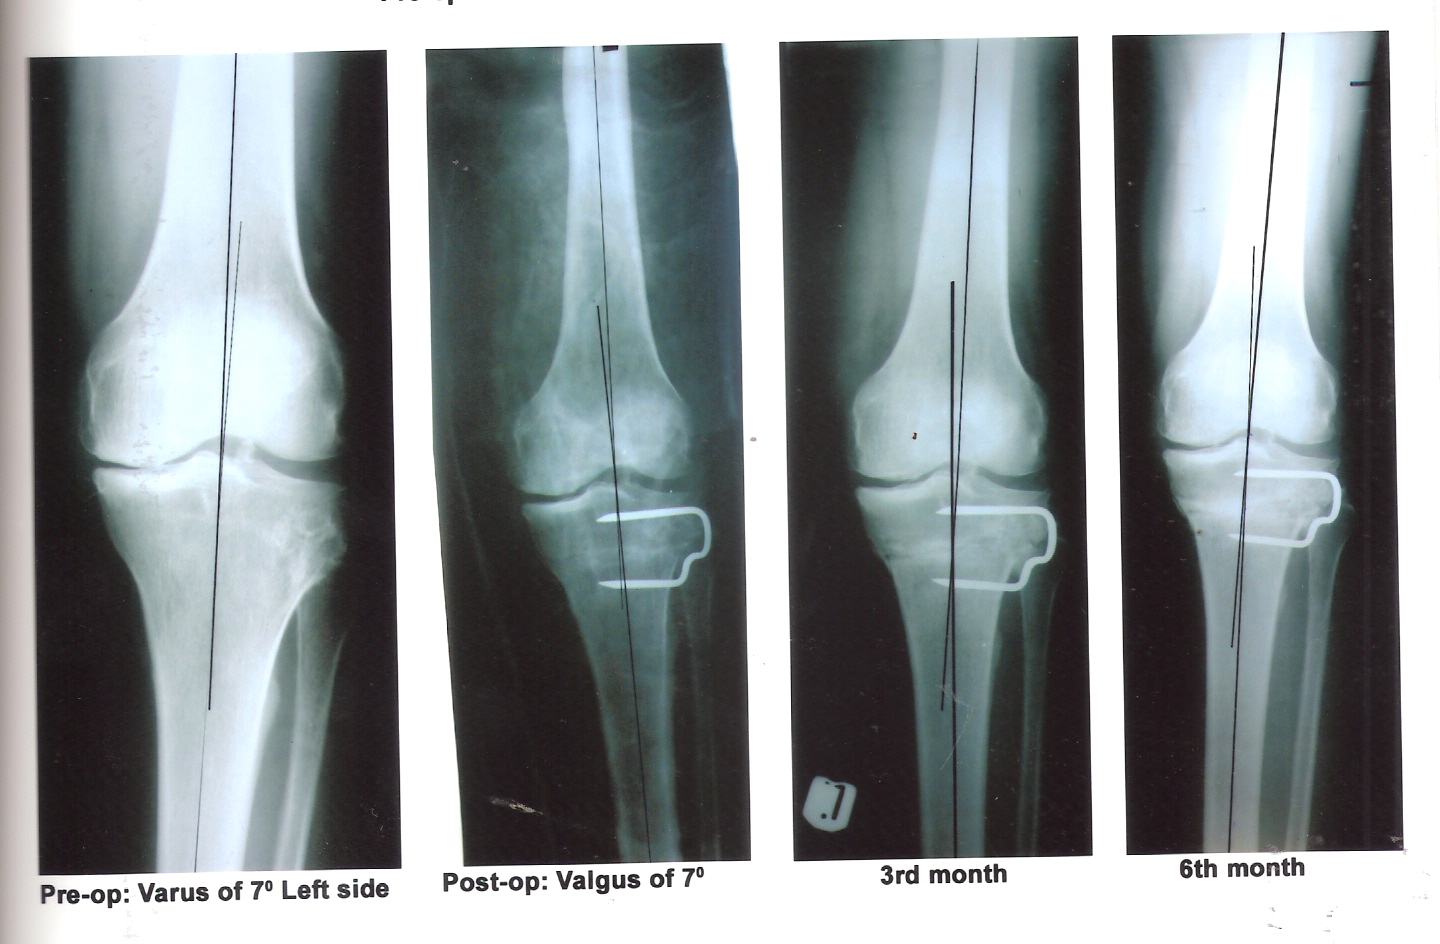

Introduction: Osteoarthritis of the knee is a common orthopaedic condition. Medial compartment osteoarthritis results from undue stress on the medial compartment of the knee joint following varus deformity. High tibial osteotomy (HTO) has been a long-standing treatment for osteoarthritis of the medial compartment of the knee. Although knee replacement has gained wide popularity for its treatment, still HTO is a good and cost effective procedure for young patients having good range of motion and uni-compartmental involvement. Objective: To evaluate the results of HTO in medial compartment osteoarthritis. Methods and Material: This study was conducted in a tertiary care teaching hospital of North India over a period of 3 years. The patients with disabling knee pain due to medial compartment osteoarthrosis with genu varus deformity refractory to conservative treatment were treated by High Tibial Osteotomy. Results: Overall 40 patients with medial compartmental osteoarthritis were treated with HTO. Patients were evaluated for the severity of pain as per Visual Analogue Score (VAS). There was satisfactory pain reduction (up to 80%) in most of the patients. Conclusions: HTO is a good procedure for young patients with good range of motion and changes confined to one compartment only.